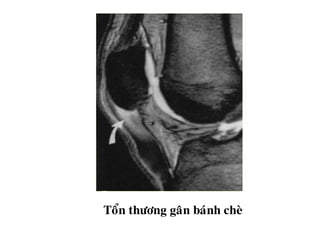

Toån thöông gaân baùnh cheø

Tổn thương chópxoay - Raùch gaân hoaøn toaøn - Raùch gaân moät phaàn: o+ Raùch maët khôùp o+ Raùch maët hoaït dòch o+ Raùch noäi gaân